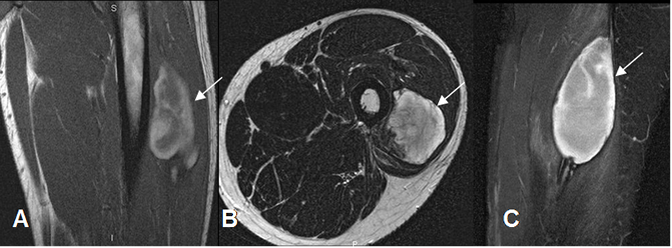

Fig 209 B. Hematoma muscular subagudo.

A: RM coronal en T1. Colección heterogénea en el músculo vasto externo, con áreas hiperintensas por evolución subaguda.

B: RM axial en T2 y C: RM sagital en STIR. Colección intramuscular, definida e hiperintensa.